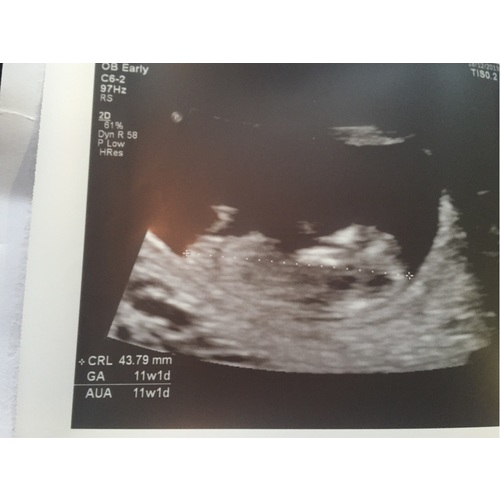

Hier 11 weken en 5 dagen.. Wat denken jullie? 😍